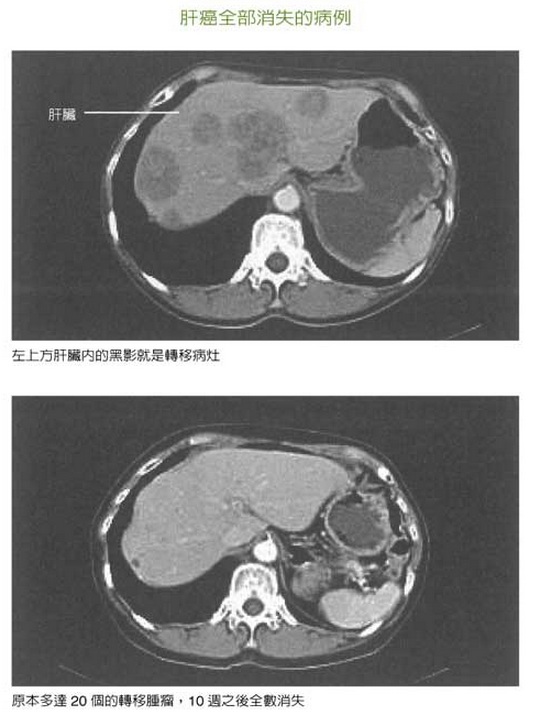

圖:肝癌全部消失的病例

(上圖)左上方肝臟內黑影即為轉移病灶/(下圖)20個轉移腫瘤,10週後全部消失